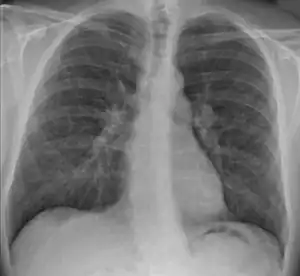

| Chest X-ray showing the typical nodularity of sarcoidosis, predominantly in the bases of the lungs. | |